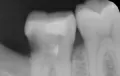

Недавно я обращалась в несколько стоматологий. Мне сказали, что в зубе развивается кариес, и стенки его тонкие. Одни предлагали поставить штифт и новую светоотвердевающую пломбу. Другие говорили, что необходим штифт и коронка.

Только штифт ставить не нужно. Необходимо восстановить коронковую часть зуба вкладкой, а затем установить коронку. В противном случае, установив штифт и пломбу, Вы рискуете и далее крошить стенки зуба, тем самым потеряете его. Обратитесь к частному стоматологу и протезируйтесь.